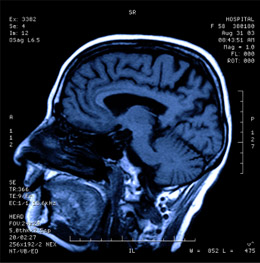

Иследователи из хайфского Техниона сумели обнаружить в человеческом мозгу нейронную активность, непосредственно связанную с речью. Открытие может способствовать возвращению способности говорить у больных при помощи вживления в головной мозг электродов, передающих электроимпульсы мозга на специальный анализатор.

Ученые из Техниона – профессор Шай Шохам и доктор Ариэль Танкус в сотрудничестве с профессором Калифорнийского университета в Лос-Анджелесе Ицхаком Фридом опубликовали в научном журнале Nature Communications свое исследование о путях расшифровки сигналов нейронных клеток в различных областях человеческого мозга, их движения в момент речевой деятельности. Это позволит распознать содержание речи пациентов на основе одной только электрической активности мозга. Практическим применением этого знания может стать создание интерфейса между мозгом и компьютером, с помощью которого можно наладить общение с парализованным больным.

При целом ряде заболеваний больные, сохраняя способность воспринимать информацию о внешнем мире, лишены возможности общаться с окружающими, поскольку их речь заблокирована. Человек не в состоянии озвучить свои мысли, хотя его разум функционирует. По словам профессора Шохама, задачей исследования является возвращение пациенту возможности речевого общения с окружающим миром посредством вживления электродов в мозг, декодирование электрической активности и искусственное воспроизведение звуков речи. Для этого прежде всего нужно было понять, каким образом информация, содержащаяся в слоге кодируется и выражается в электрических импульсах клеток мозга.

Исследования проводились на базе медицинского центра Калифорнийского университета, и в них принимали участие больные эпилепсией, которым вживили микроэлектроды в мозг с целью определения источника эпилептического припадка. После операции больные были госпитализированы на протяжении одной-двух недель и наблюдались на предмет возникновения спонтанных эпилептических припадков, которые записывались через электроды специальным устройством. С помощью этих же электродов ученые могли следить и за активностью в слуховой зоне. Пациентов просили произносить отдельные звуки – гласные и согласные, – слоги и более сложные сочетания звуков. Одновременно записывалась активность нервных клеток. Исследователи обнаружили наличие двух «популяций» нервных клеток, каждая из которых кодировала движение нейронов отличным от другой образом.

При изучении соотношения между активностью нервных клеток и артикуляцией, то есть работой речевых органов, удалось обнаружить и описать математическую зависимость между движением нейронов мозга и человеческой речью. Таким образом, можно охарактеризовать эти исследования как важный шаг на пути к расшифровке клеточной активности при помощи компьютера, который позволяет обеспечить высокую скорость распознавания импульсов и наладить полноценное общение с человеком, чей мозг функционирует, а речевой центр блокирован.